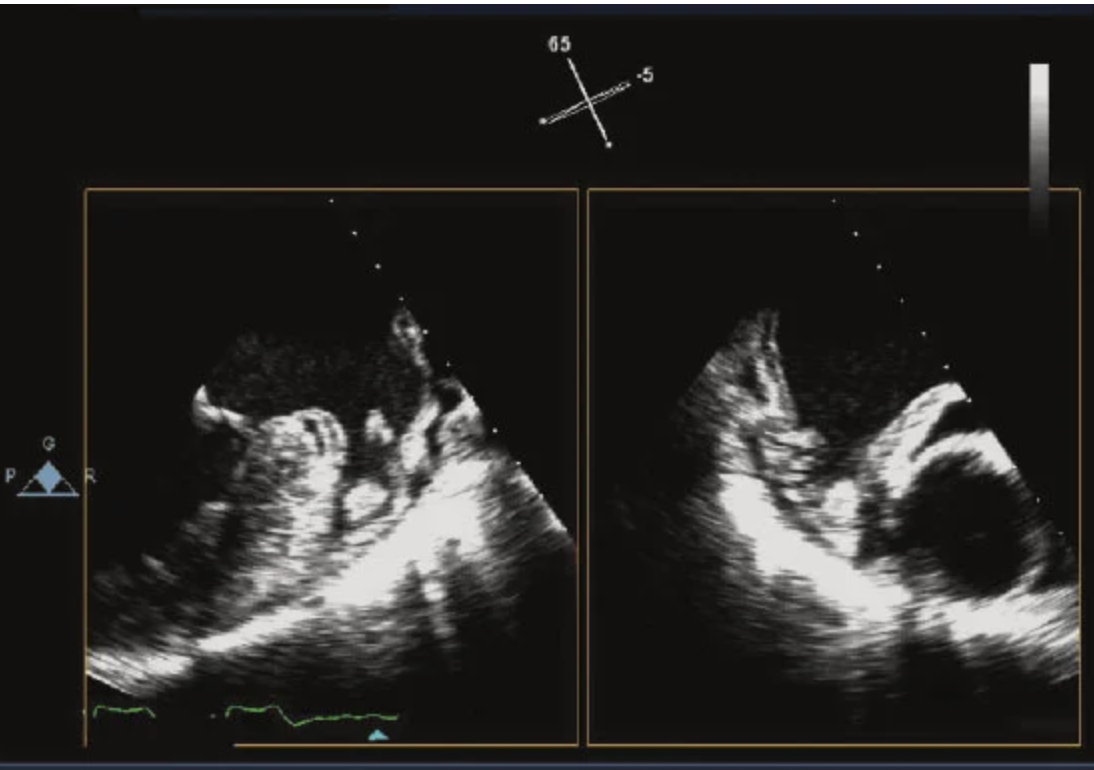

27

These images were acquired minutes apart. What is the most likely explanation for the difference?

The answer is a change in equipment settings, in particular, the Nyquist limit. This is a frequent mistake in evaluating regurgitant lesions. The appearance of a jet by color Doppler depends on jet momentum (flow × velocity). In addition, changes in gain, pulse repetition frequency, and Nyquist limit may markedly change the size of the jet. The standard Nyquist limit to evaluate a regurgitant lesion is around 45–60 cm/s. In this particular example, the Nyquist limit was lowered to interrogate the interatrial septum (low-velocity patent foramen ovale [PFO] flow) and then was not changed back to assess the degree of mitral regurgitation.